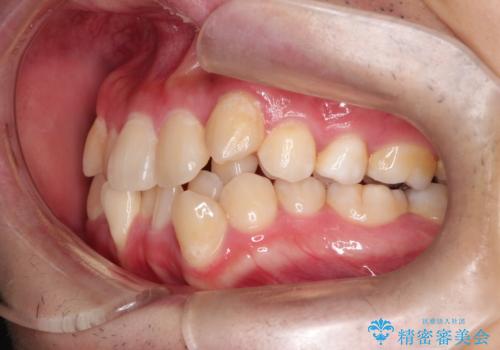

【重度叢生ワイヤー矯正】きれいな歯並びにしたい

- きれいな歯並びにしたいとの希望を持って来院された患者様です。

上下左右小臼歯を抜歯する治療計画を立て審美装置にて治療を行いました。

骨格的3級傾向もあり、咬合関係を仕上げるのに時間がかかりましたが、患者様には大変満足していただけました。